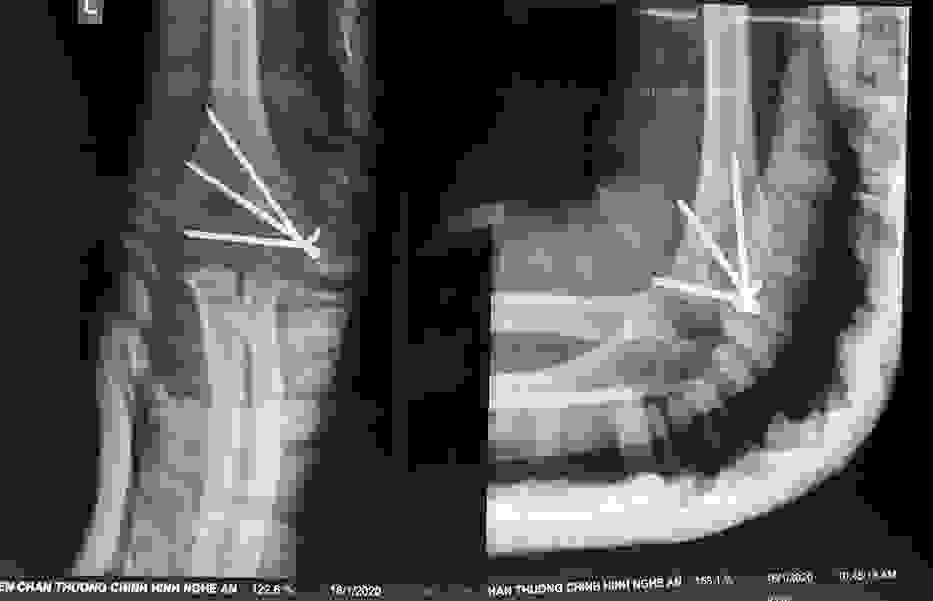

Phẫu thuật thành công ca bệnh hiếm gặp...khớp giả bẩm sinh xương chày

26/06/2019 17:00

Đã xem: 3735

Bệnh viện Chấn thương- Chỉnh hình Nghệ An, vừa phẫu thuật thành công cho bệnh nhi khớp giả bẩm sinh xương chày